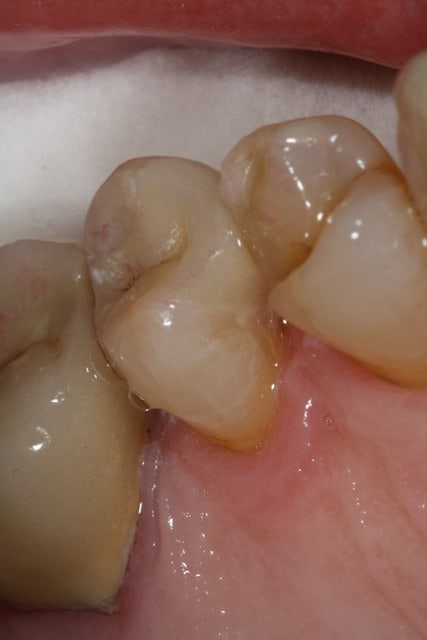

Puisque tout le monde montre des photos, à mon tour.

Il m'aura quand même fallu un petit moment avant de réussir à faire des onlay qui ressemble à quelque chose... Comme quoi, c'est pas que le prothésiste qui bosse!

Par contre me former ça commence à me coûter cher... Je ne fait presque plus de SPR50/SPR57...